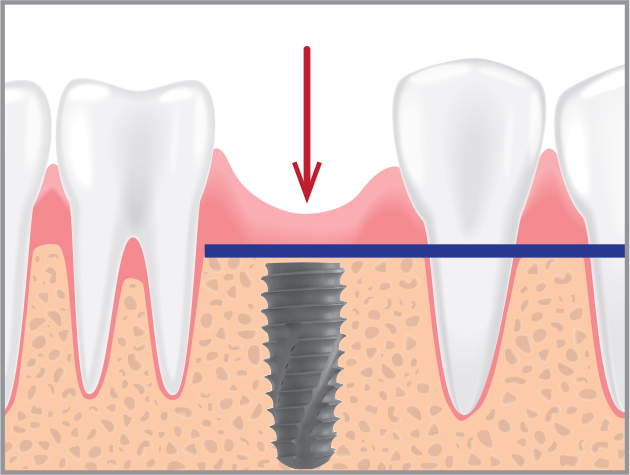

Implant 식립 깊이

전후 Bone Level보다 1~2mm 깊게

BOSS Abutment 높이

전후 치은 높이보다 1mm 낮게

BOSS Abutment 선택

치은 높이에 따라 BOSS Abutment 선택